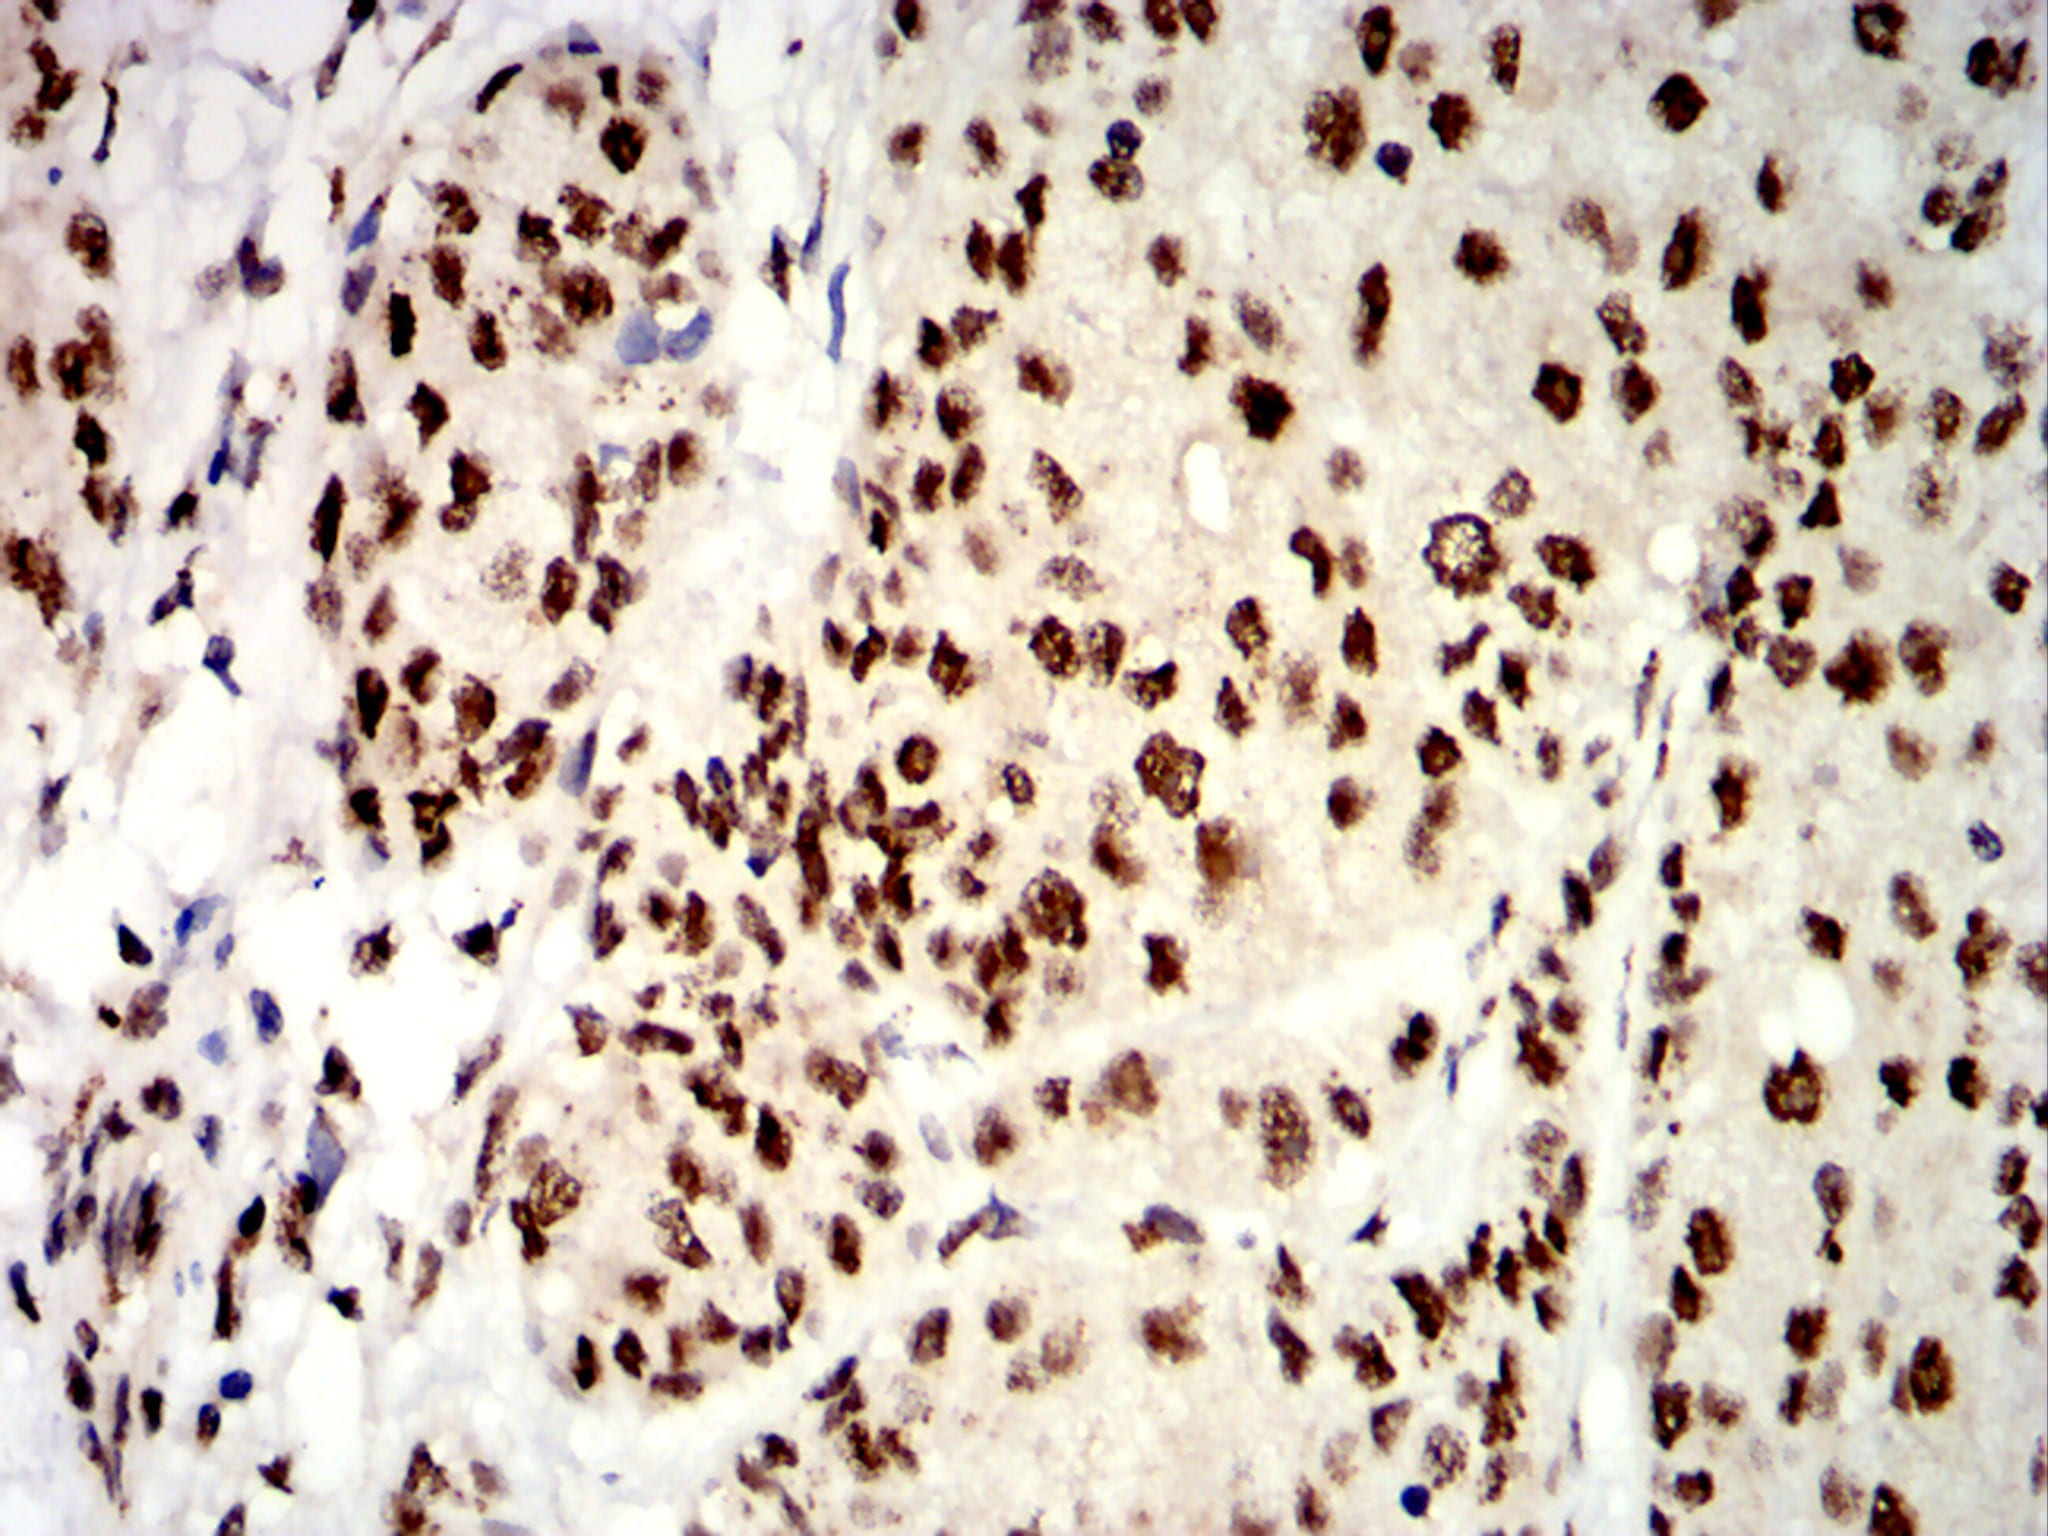

Immunohistochemical analysis of paraffin-embedded human bladder cancer tissues using UHRF1 mouse mAb with DAB staining.

-

Immunohistochemical analysis of paraffin-embedded human esophageal cancer tissues using UHRF1 mouse mAb with DAB staining.